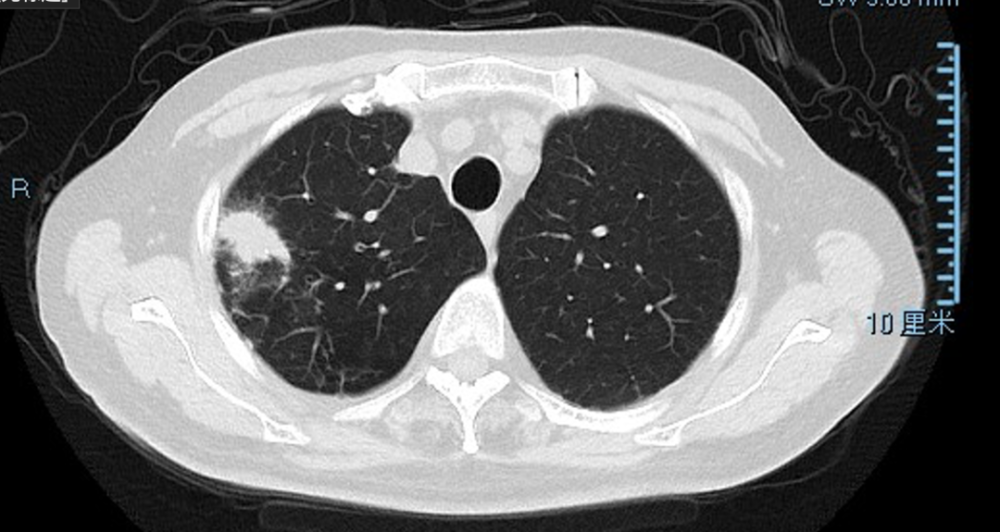

胸部CT(2021-1-25)